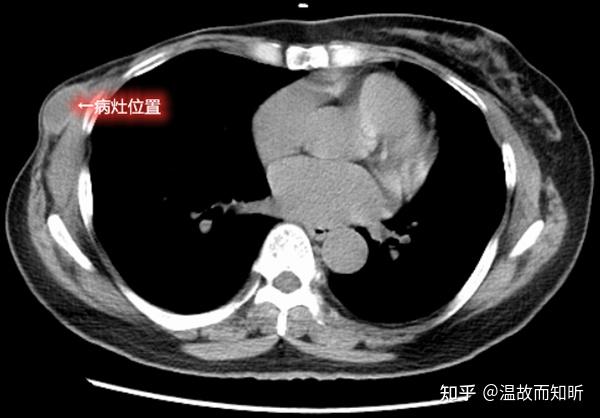

10年前因左侧乳腺癌在外院接受手术治疗,术后肿瘤复发,先后2次在其他